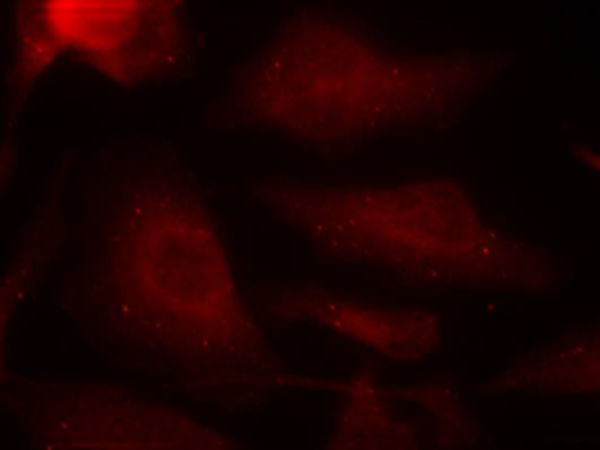

IF Positive control: |

Hela cells |

IF Recommended dilution |

100-200 |